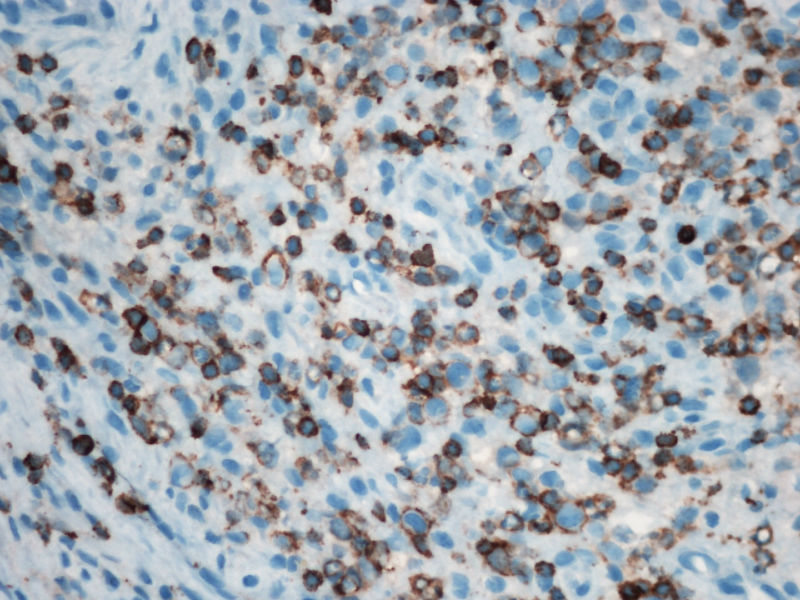

的确如此,CD43不仅表达于多量T细胞淋巴瘤,还可以表达于一些B细胞淋巴瘤,如套细胞淋巴瘤、小淋巴细胞淋巴瘤/白血病、粒细胞肉瘤等等,甚至还可以表达于一些非肿瘤细胞。本例CD2,CD3,CD4,CD8,CD5,CD7均阴性,在这样的大细胞病变形态基础上,此时做CD43和细胞毒标记物只是寻找诊断ALCL的佐证,后来果然CD43和部分细胞毒标志物是阳性,对于“裸”免疫表型的ALCL,这一诊断思路也是WHO和许多文献推荐的,日常工作中也是我们也常常是这样做的。如果病变是在淋巴结内,HE是大细胞病变,且出现上述免疫表型,我想应该有许多病理医生就诊断了ALCL了。只是本例部位等临床特征特殊,诊断需要慎之又慎,但最后ALK-1也显示大细胞阳性,就增加了诊断的信心。

1.关于CD15:可见于HL,偶尔(WHO: rarely)见于ALCL,甚至可意外地或异常地(WHO: exceptionally)见于外周T,非特指.

2.关于PAX5:应该是HL和ALCL鉴别非常好的标记。WHO: The B-cell nature of HRS cell is further demonstrable in approximately 95% of cases by their expression of the B-cell specific activator protein PAX5. 本例PAX5阴性,重点就只有放在ALCL上了。

3.关于CD43: 对比CD43和CD3的结果,并不能否认ALCL,甚至还提供了一个线索就是CD3- 是由于肿瘤细胞“改头换面”缺失表达造成的,如果追加CD2,4,5等可能就会使肿瘤“原形毕露”了。

最后,ALK+可证实以上的推断。

2)肿瘤细胞免疫表型特殊, CD30+CD15+ALK-1+CD43+Perforin+, 而其他PanB细胞和PanT细胞的标记均为阴性。

关于第二个问题:

本例是大细胞病变;本例出现了“裸”免疫表型,这可在ALCL中出现;本例perforin阳性,支持是细胞毒性的大细胞淋巴瘤;大细胞同时表达CD30/CD15/ALK/细胞毒标志物,据目前文献报道,只有ALCL能解释;EBER阴性;临床影像学提示为溶骨性病变。。。